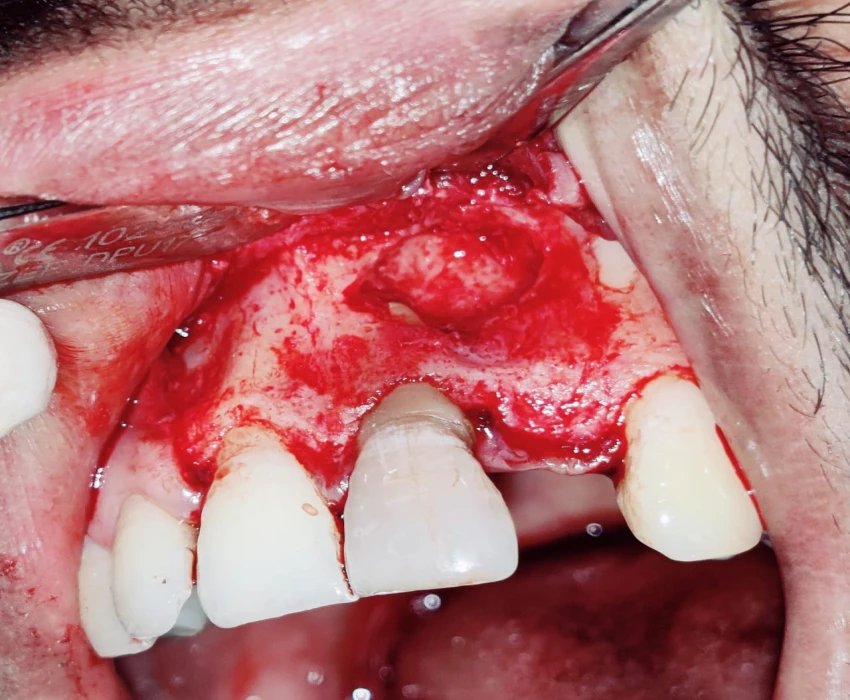

TREATMENT- Faulty prosthesis is removed in respect to 22, with the help of tapered fissure. Access Opening is done' in respect to 21, under La. Working length is determined . Canals are prepared using Hyflex CM and obturated using Gutta percha using lateral condensation. Microperiosteal flap is raised. Window preparation irt 21 , periapical curretage apicoectomy is done irt 21 followed by retrograde filling with bioceramic. Cavity is filled with bone graft. Sutures placed.